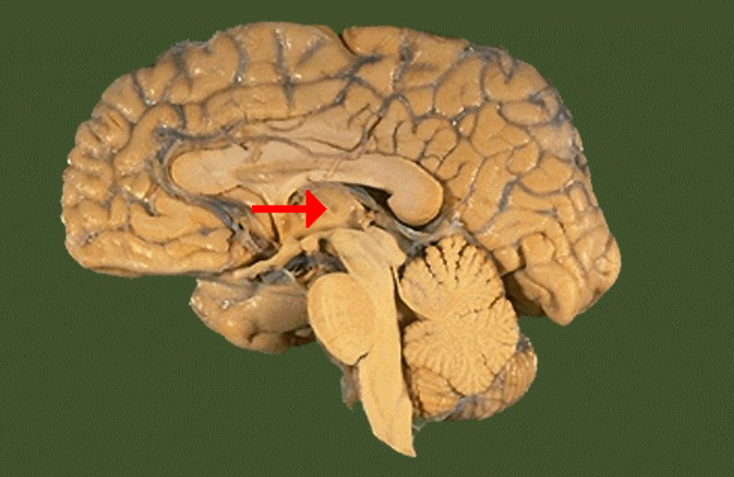

Label this brain part

Corpus callosum

Label this brain part

Mammillary body

Label this brain part

Cerebellum

Label this brain part

Aqueduct of Sylvius